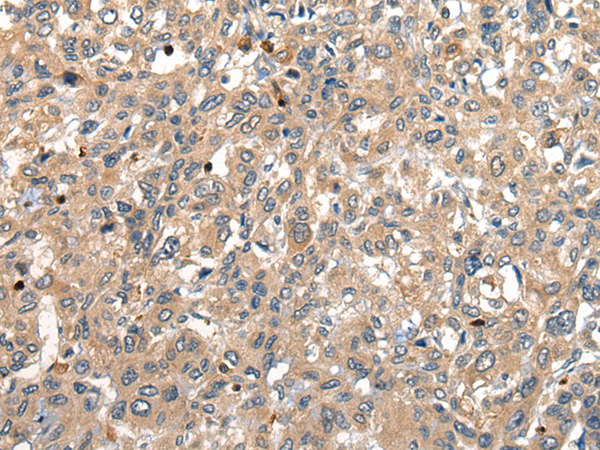

IHC positive control: |

Human liver cancer |

IHC Recommend dilution: |

25-100 |